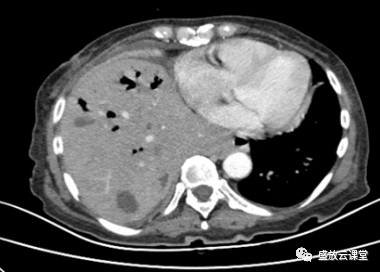

【病例】肺淋巴瘤(MALT)一例CT影像

【病例】肺淋巴瘤(MALT)一例CT影像-3 【病例】肺淋巴瘤(MALT)一例CT影像-4

【病例】肺淋巴瘤(MALT)一例CT影像-2